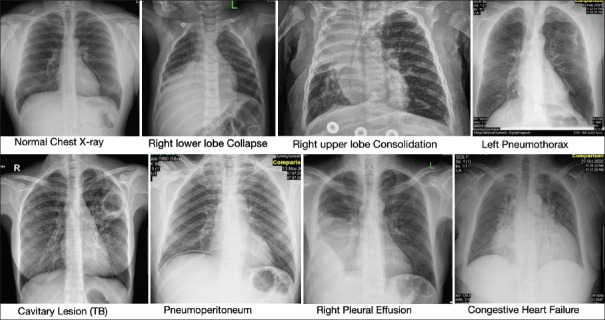

Abstract Image